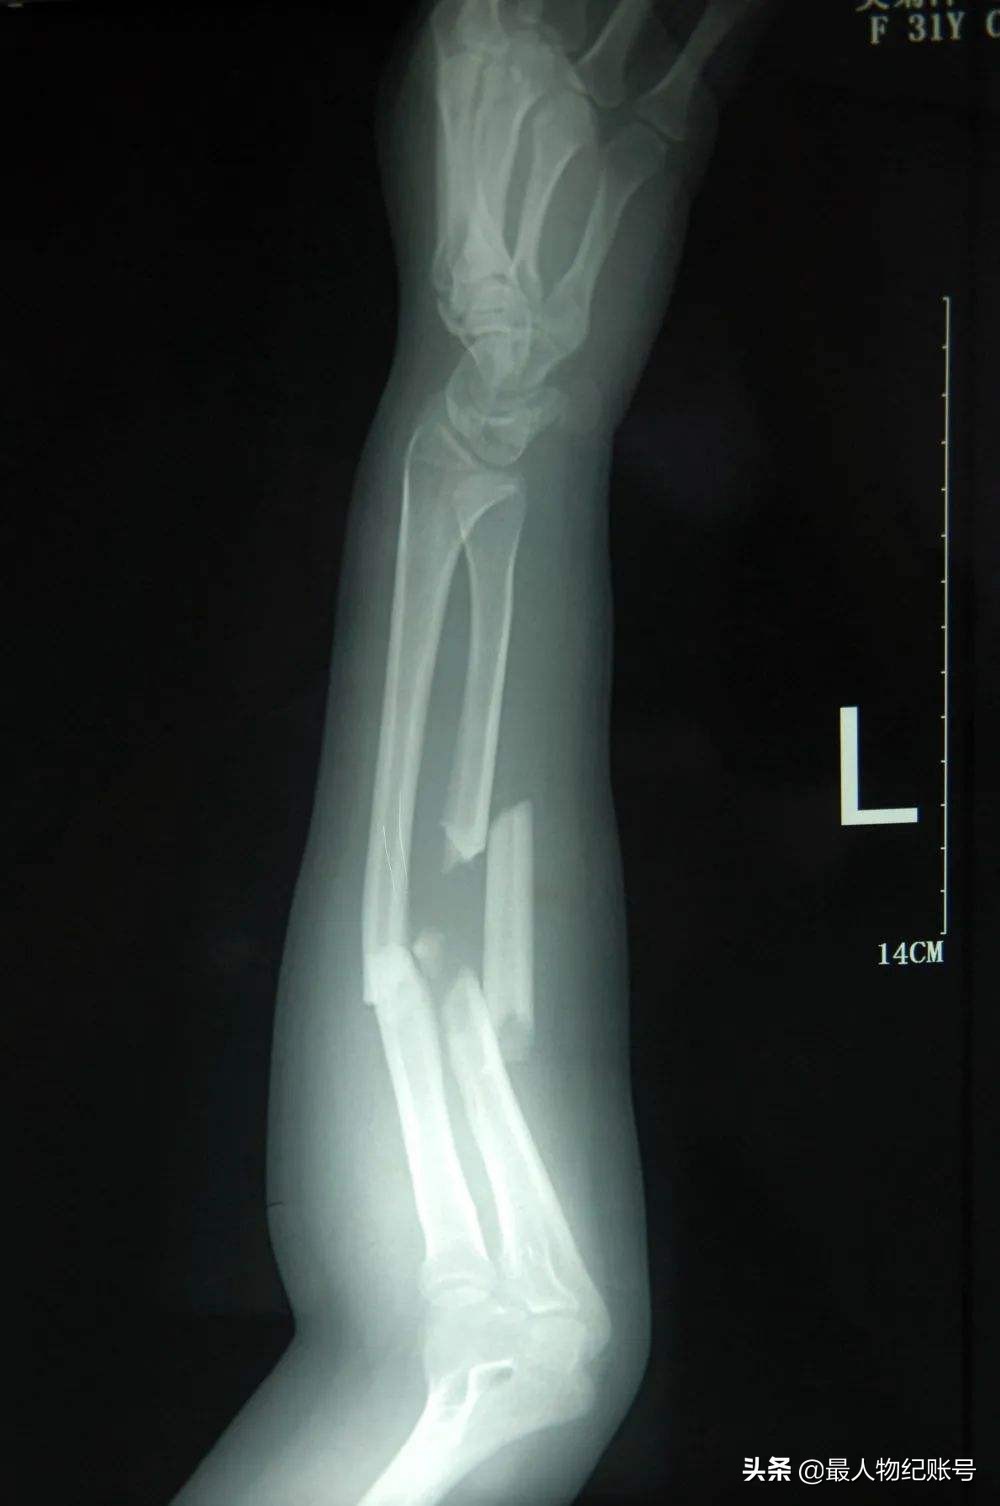

吴菊萍的X光

而吴菊萍经过医生检查后,她左臂的尺桡骨断成了三截,有骨头断端戳出皮肤出来,伤势非常严重,需要立即手术。无奈之下,吴菊萍只好向公司请了两个月的长假,医院也连忙为她做了手术。